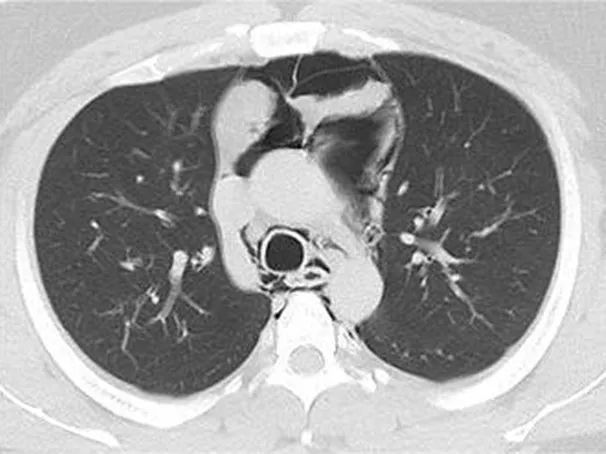

一个月前的晚上小明剧烈撸铁后顿感胸部不适,胸闷、胸痛,第二天下午胸闷、胸痛等症状持续加重,并且开始气急气促,小明当天傍晚来到瑞金医院嘉定院区急诊科就诊,CT检查结果显示小明胸部出现了“纵隔气肿”。

急诊立即请胸外科张能冲医生会诊。张能冲医生诊断小明为剧烈举铁摒气引起的胸腔压力骤增导致的自发性纵隔气肿,推入急诊抢救室对症处理,但小明逐渐出现心率加快(超过130次/分),呼吸急促(频率超过30次/分),氧饱和度需要面罩吸氧及增加吸氧浓度才能维持在95%左右,无法平卧,大汗淋漓,复查胸部CT提示纵隔气肿较前明显进展,双侧气胸。

初诊CT显示纵隔气肿明显